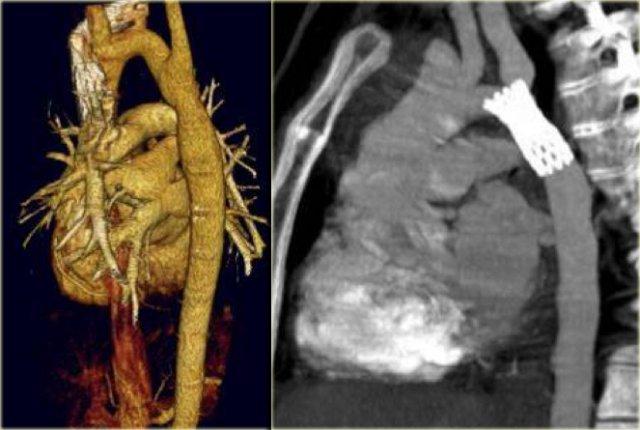

On the left an adult who was operated in his childhood for a Tetralogy of Fallot (pulmonary stenosis, right ventricular hypertrophy, VSD, overriding aorta).

At surgery the VSD was patched and the pulmonary outflow tract was enlarged.

Notice that there is also a right arch.

In the United States there are now more than one million adults who have survived their congenital heart disease.

In the ER you will see these patients because they age and get chest pain like many adults do and so you will see these anomalies more frequently.